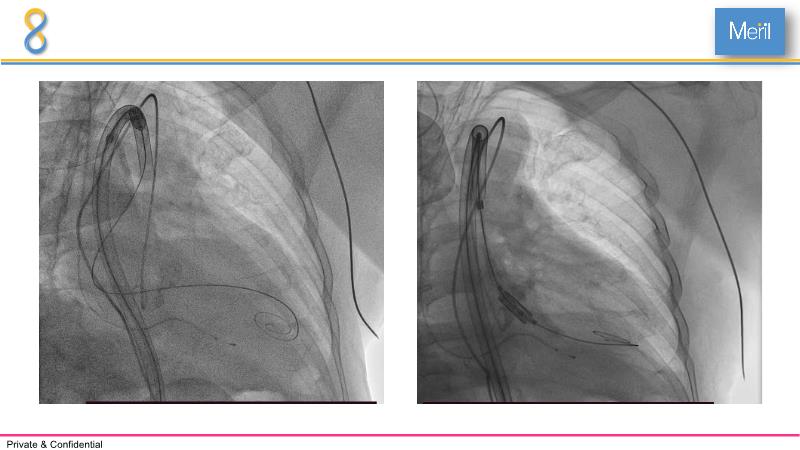

Through the presentation of several compelling cases, including an 88-year-old male with CKD, RBBB, moderate LV dysfunction, and severe aortic stenosis, a Type 1a bicuspid native AS, and an extraordinary TAVI in an 83-year-old with acute heart failure and comorbidities, this session will dive into the Myval Octapro THV. Learn about its key features, procedural impact, and potential clinical benefits. Discover the Octalign technique for predictable and precise commissural and coronary alignment, preserving coronary access. Gain insights into precise sizing, positioning, and deployment of the Myval THV series in real-world scenarios, and explore the relevance of pivotal Landmark RCTs in clinical practice.

- To know the Octalign technique which enables predictable and precise commissural and coronary alignment thus preserving coronary access

- To understand the technique of precise sizing, positioning and deployment of Myval THV series in real world clinical scenarios